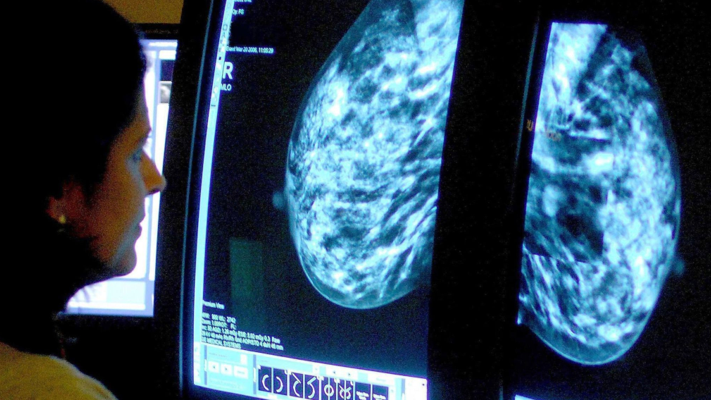

그리고 결과는 ‘검진 시점’과 ‘검진 사이’에서 갈렸다.

AI 그룹에서는 암 사례의 81%가 검진 시점에 발견됐고, 표준 검진 그룹에서는 74%가 그 시점에 발견됐다.

검진 사이 기간에는 AI 그룹이 여성 1,000명당 1.55건, 대조군은 1,000명당 1.76건의 암이 발견됐다.

핵심은 이 차이가 ‘사이암 감소(12%)’로 이어졌다는 점이다.

연구에 따르면 표준 검진과 비교했을 때 AI 그룹에서는 침윤성 암이 16% 더 적었다.

큰 종양은 21%, 공격성이 높은 암은 27% 더 적었다.

AI 지원을 받은 경우 암이 더 이르고 치료 가능성이 높은 단계에서 포착되는 경향도 관찰됐다.